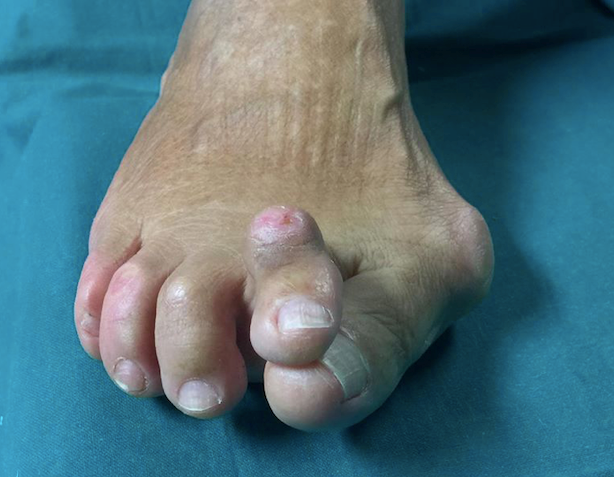

L’alluce valgo è una deformità progressiva del piede che si manifesta con la deviazione mediale del primo metatarsale e deviazione laterale della prima falange verso le altre dita.

Questa anomalia crea una sporgenza ossea, comunemente chiamata “cipolla”.

Ciò provoca un sovraccarico delle dita adiacenti e della pianta del piede, con possibili conseguenze, come la formazione di calli dolorosi (metatarsalgia) e dita incurvate (dita a martello).

L’alluce valgo è una patologia complessa. Trattandosi di una deformità multiplanare, i segnali di allarme non riguardano solo la deviazione laterale (verso le altre dita), ma anche la rotazione dell’alluce.

- Rotazione (multiplanarietà): la rotazione del dito può causare problemi all’unghia (come onicopatia), che può incarnirsi o diventare più scura. Spesso questi sintomi non traggono beneficio dalle comuni cure dermatologiche.

- Callosità compensatorie: a causa della metatarso-falangea deformata e inefficiente, le articolazioni adiacenti (tra le falangi) sono costrette a iperfunzionare. Ciò si traduce nella formazione di un callo tra falange e falange, un segno del tentativo di compensazione da parte del piede.